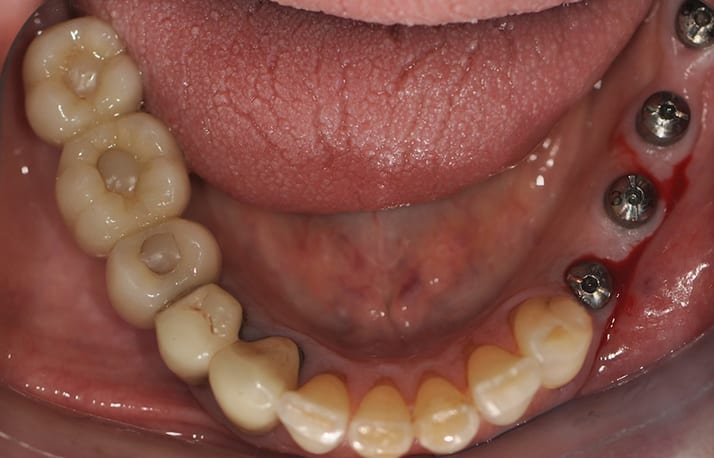

Ze comprends pas. C’est très zoli. Mais c’est cassé et ça me coupe la langue .

Un ptit coup d’oeil en bouche

1) oh dis donc une couronne sur Implant. Comme par hasard...

2) oh tiens c’est une transvissée

3) oh tiens une tout céramique

4) oh mince alors comme c’est bizarre Zircone + cosmétique

5) oh ! En postérieur ! Tiens donc !:)))

6) oh Bin mince alors une brachyfaciale avec des beaux masseters

Ze comprends vraiment pas ! Suis toute paniquée ! Suis toute émotionnée de partout! Comment l’expliquez vous docteur ? Je ne sais pas madame mais effectivement il faut refaire, ça arrive , c’ est la faute à pas de chance, ne vous inquiétez pas, on va faire un autre type de couronne

Sur ta photo , c’est du biomet3i Smith et wesson ?

Bande de nazes ;0)) c’est du Google , je ne fais que du scellé pour cette raison !

Oui mais n’empêche que je dirais bien que c’est du biomet 3i